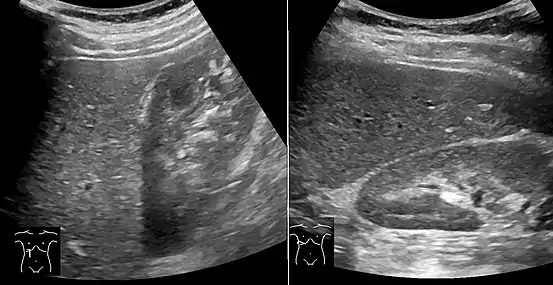

Liver steatosis (fatty liver disease) as seen on CT

On X-ray computed tomography (CT), the increased fat component will decrease the density of the liver tissue, making the image less bright. Typically the density of the spleen and liver are roughly equivalent. In steatosis, there is a difference between the density and brightness of the two organs, with the liver appearing darker.[12] On ultrasound, fat is more echogenic (capable of reflecting sound waves). The combination of liver steatosis being dark on CT and bright on ultrasound is sometimes known as the flip flop sign.

On abdominal ultrasonography, steatosis is seen as a hyperechoic liver as compared to the normal kidney.